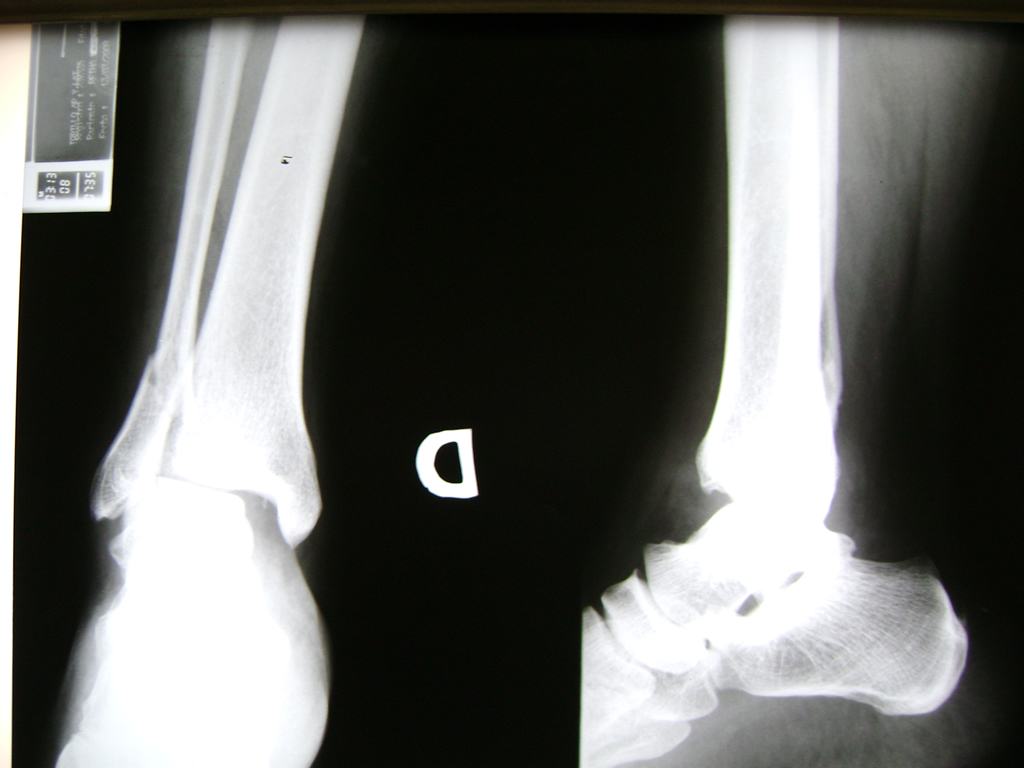

Calcaneo - Tobillos

Una fractura de tobillo es la rotura de uno o más de los huesos del tobillo. Estas fracturas pueden ser:

Algunas fracturas de tobillo pueden requerir cirugía si:

- Los extremos de los huesos están desalineados entre sí (desplazados).

- La fractura se extiende hasta la articulación del tobillo (fractura intra-articular).